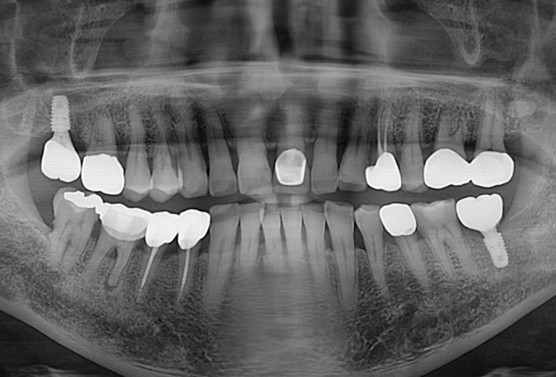

[2021.11.23 처음 내원 시 찍은 파노라마 사진]

친구 아버님이 멀리 울산에서 오셨습니다.

큰어금니가 식사할때마다 아프다고 하셨고, 씹을 때 찌릿찌릿한 느낌이 있다고 하셨습니다.